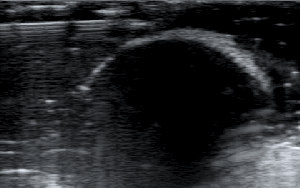

- Βάζουμε μέσα το σταφύλι.

2) Το βάθος (depth), δηλαδή το να φέρουμε στην οθόνη του υπερήχου όσο το δυνατόν πιο κοντά το αντικείμενό μας, ώστε να καλύπτει σχεδόν τα 2/3 της οθόνης μας.

Μειώνουμε το βάθος ώστε να φέρουμε κοντά μας το αντικείμενο.